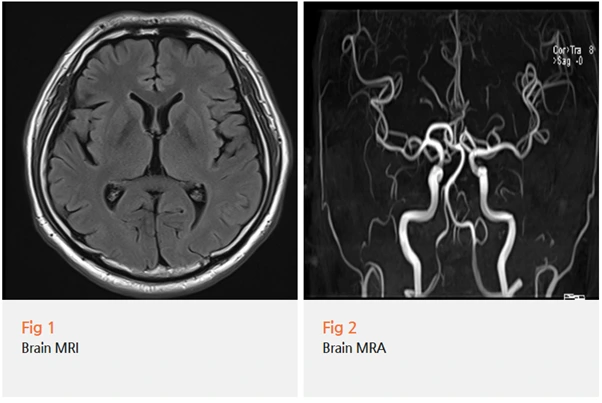

그래서 뇌 MRI랑 MRA 검사를 권해드렸어요.

근데 다행히 검사 결과는 정상이었어요.

뇌에는 아무 이상이 없었어요.